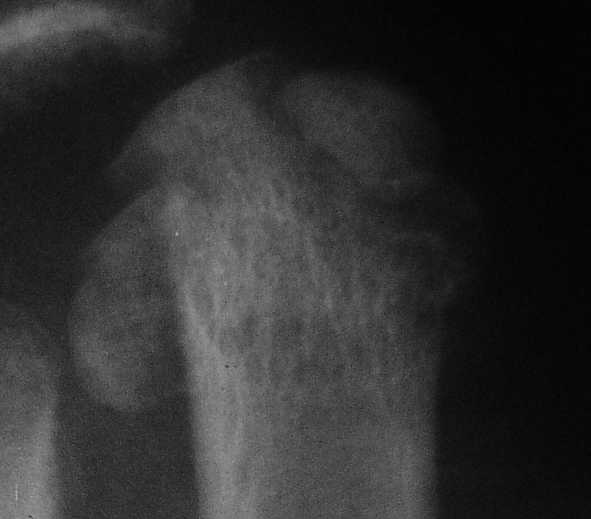

3 кстати, Вы перелом пкрвой плюсневой видите? В каком месте и на каком снимке?

Вот головка более прицельно.

Вот теперь вижу :)